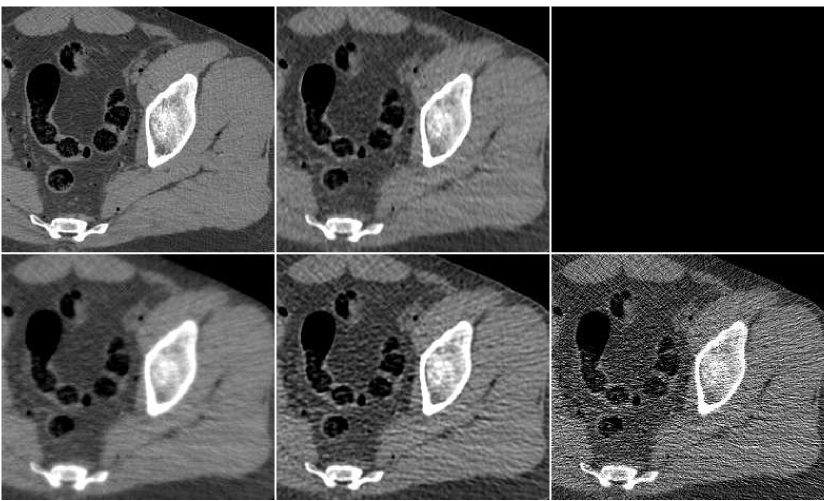

In Figure 10 we display the fusion result along with individual PWLS reconstructions, used in the fusion process. The lower part of the figure contains the absolute-valued error images. The fusion result has a higher visual quality than any of the three underlying images. Comparing to those images, the noise level in the fusion image is the lowest, and the tissue texture is closer to the original. The sharpness is the same as in the lower middle PWLS image. The SNR values (stated in the Figure) also point to the improvement in quality. The SSIM of the fusion image is , while the sequence of PWLS results have the SSIM values of (corresponding to the lower row of Figure 10, left to right). A reconstruction of an additional test image is displayed in Figure 11. The effect of the fusion observed here is similar to the one in the previous reconstruction. We conclude that the ANN-based fusion can contribute also to the iterative reconstruction, without requiring any additional iterations; the computational cost of the fusion, exercised after the reconstruction, is lower by an order of magnitude than that of the iterative process.